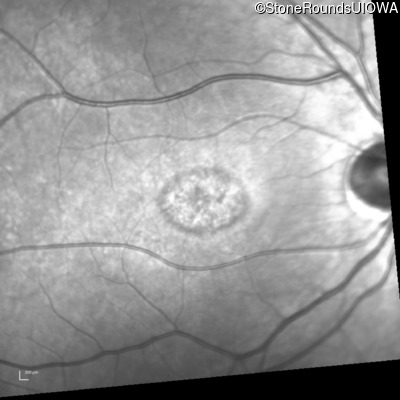

Infrared Fundus Photograph - Left - 20/50 +2

Exemplar